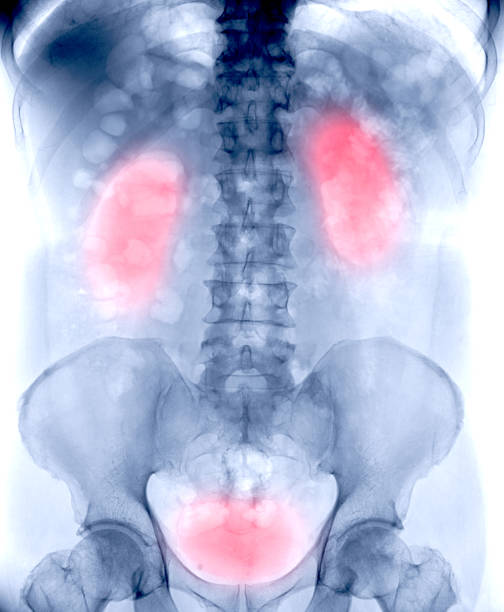

- 허리, 옆구리, 등 아래쪽 통증

특히 허리통증 + 발열 + 소변 이상 증상이 같이 나타난다면

신우신염 가능성을 높게 봐야 합니다.

신우신염 진단, 어떻게 진행되나요?

병원을 방문하면 간단한 검사를 통해 신우신염 여부를 확인할 수 있습니다.

- 초음파·CT

- 신장 구조 이상, 요로결석, 농양 확인